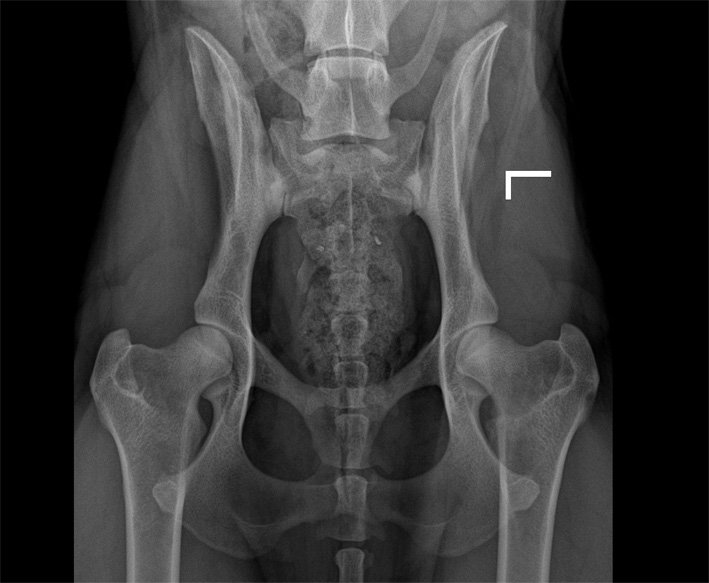

Hier nun einige HD Röntgenbilder:

![]() HD fast-normal / HD-B / HD-1 |

B |

= Übergangsform |

HD-1 |

fast-normal |

Fast normal, geringe Veränderungen an Kopf oder Pfanne, NORBERG-Winkel von mindestens 100 Grad |